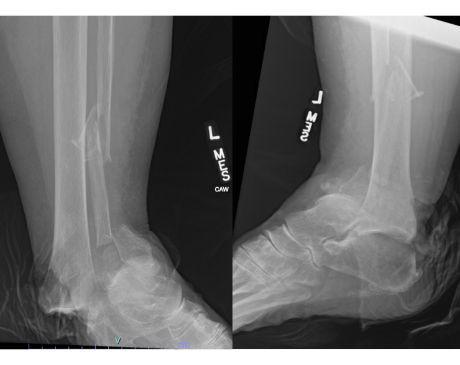

I was hit by car, had a compound fracture with a bone sticking out of my left foot. Broken tibia and fibia?. Screwed plate and bones back together. I am healing fine, next visit 3/26 to remove stiches. I seem to have total function of foot. Still have 2 more weeks of not using leg, but very hopeful.